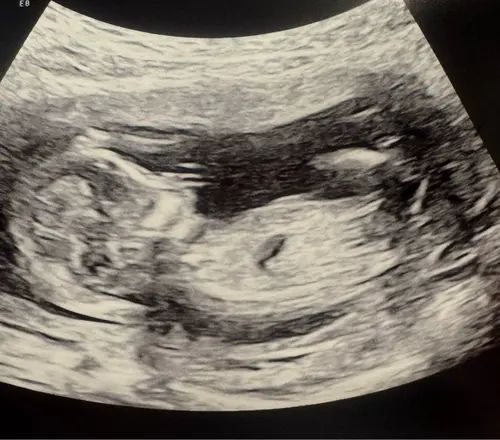

Kan iemand hier iets herkennen? Echo van 13+5

Ik vind ze alle 3 best onduidelijk

Is dit een jongen of een meisje??

Maar kan nog veranderen aangezien je nog 12+4 ben